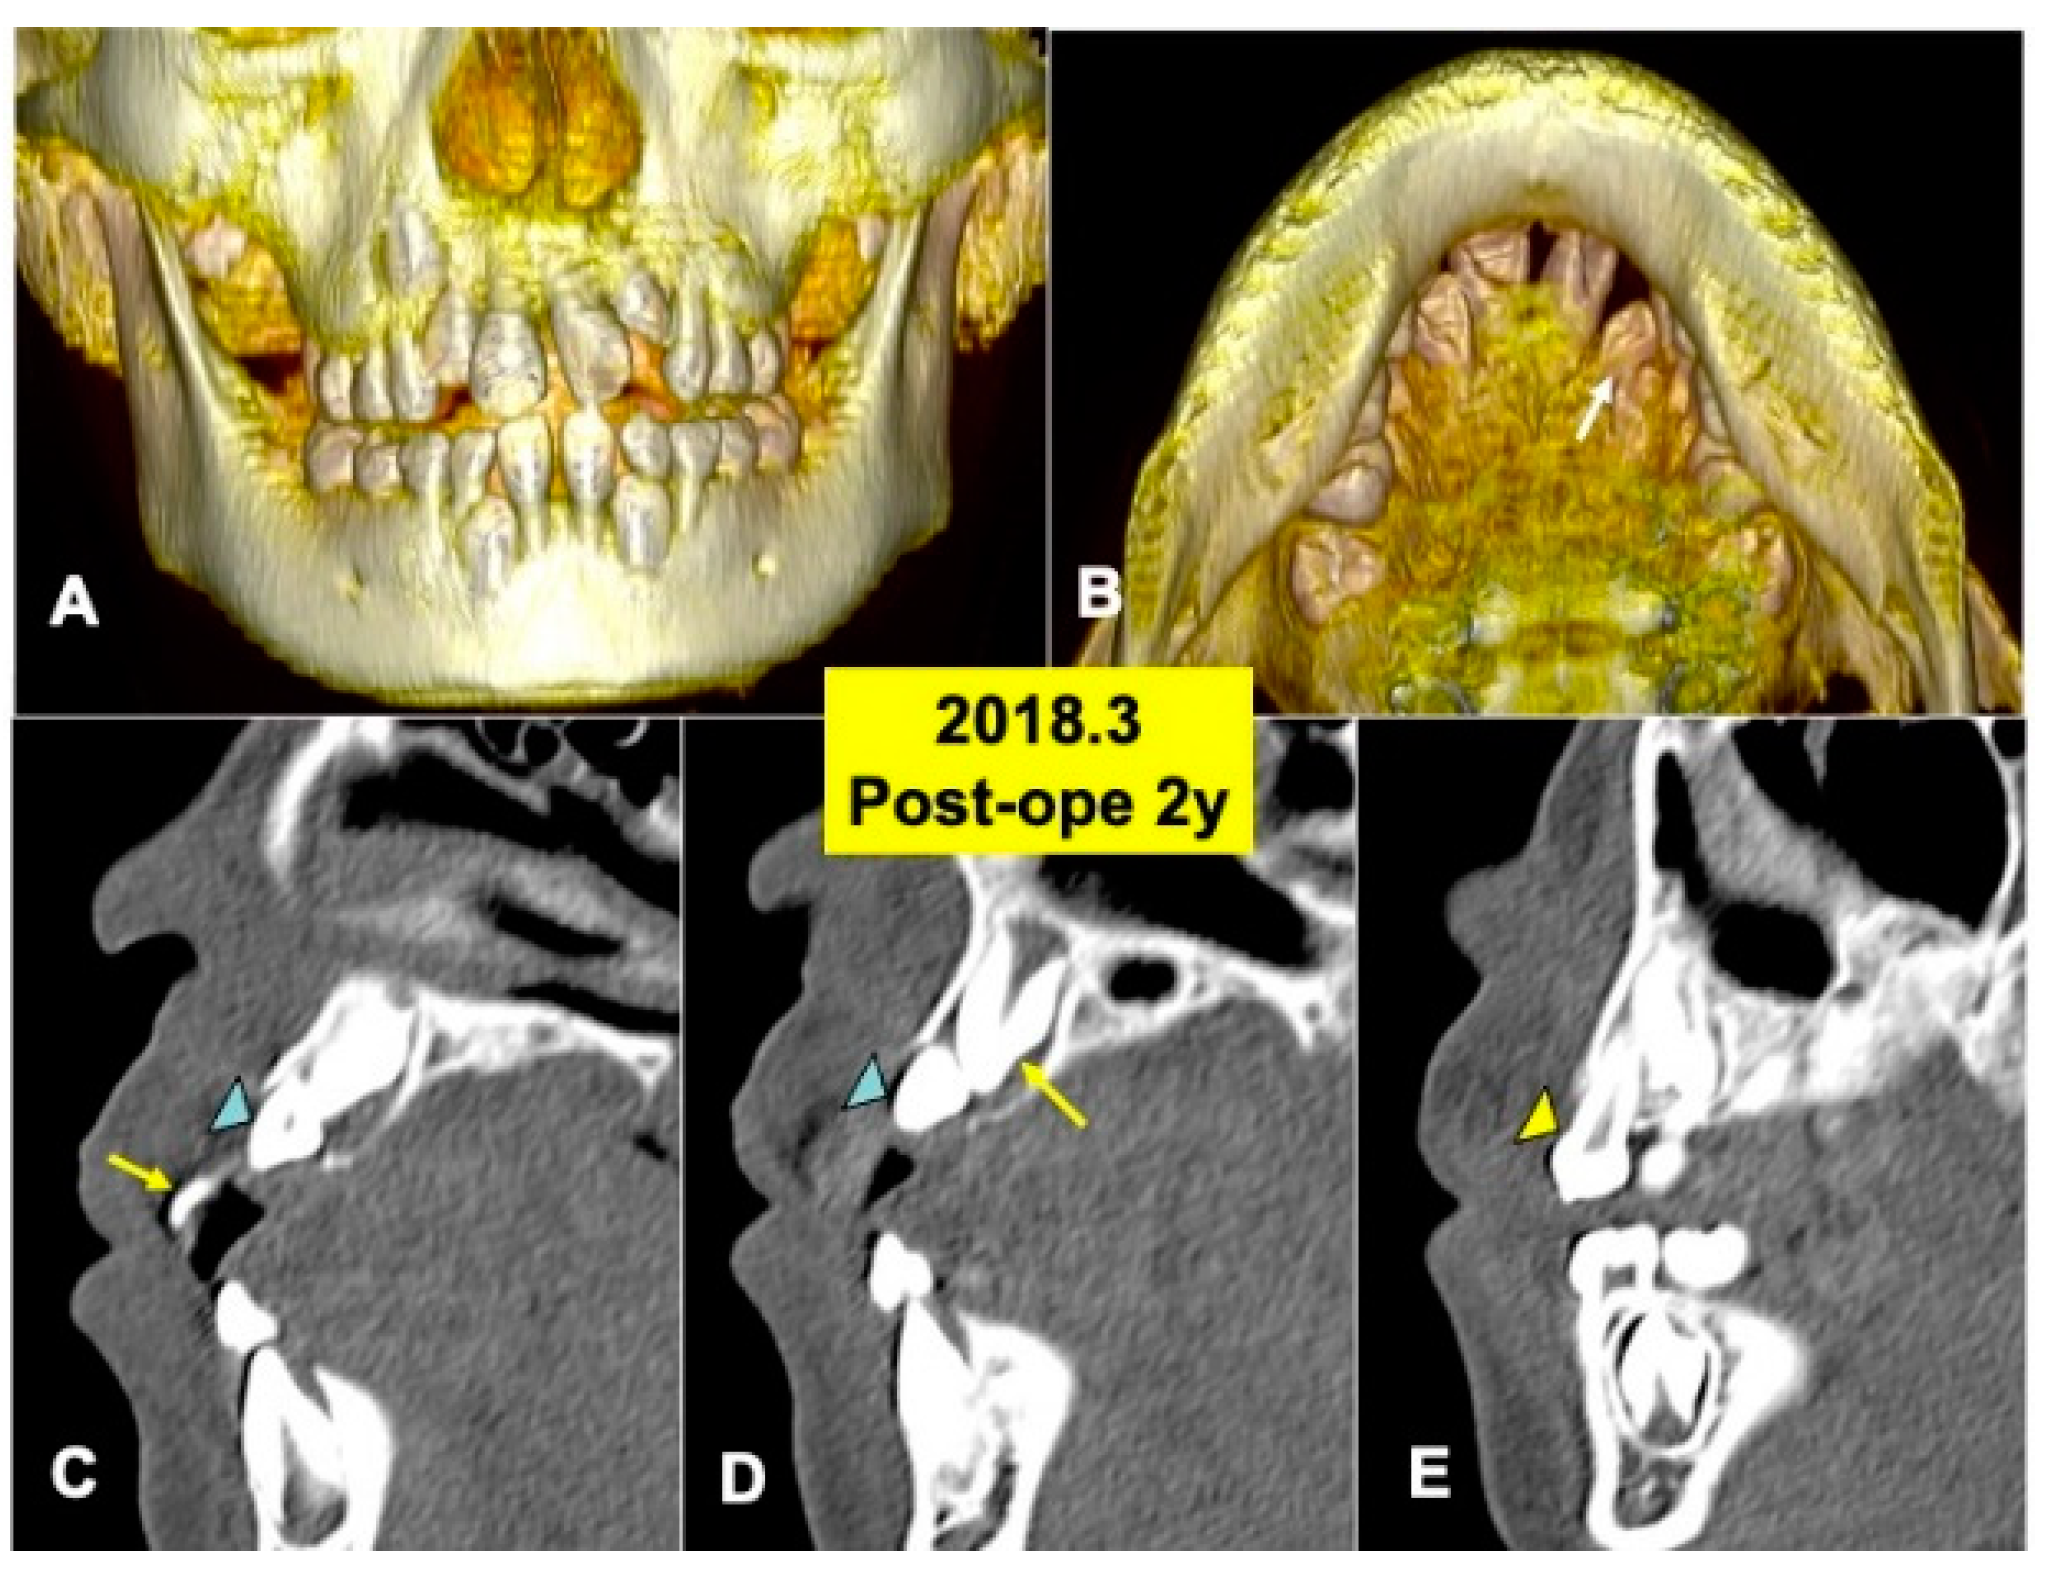

Figure 5.

X-ray CT photos at 2 years after surgery. (A) Three-dimensional (3D)-CT image. Eruption of teeth 11 and 21. (B) Three-dimensional (3D)-CT image. Arrow indicating tooth 22. (C) Sagittal appearance near teeth (22,23). Arrow indicating tooth 21. Arrowhead indicating tooth 22. (D) Sagittal appearance near teeth (22,23). Arrow indicating tooth 23. Arrowhead indicating tooth 22. Note: Flat bone contour and no appearance of DDM granules. Arrowhead indicating tooth 23. (E) Sagittal appearance near teeth (63, 23). Arrowhead indicating primary canine (63).

The 3D-CT views at 2 years after DDM graft showed a tendency of the eruption of impacted tooth 22 (Figure 5A,B). Tooth 22 before eruption was inclined distally, and tooth 22 was contacted with primary tooth 63 (Figure 5A). DDM granules were not found near teeth (22,23) (Figure 5C,D), and the smooth cortical line of alveolar bone was observed clearly (Figure 5C–E). In addition, normal spaces around the crown of tooth 23 were seen (Figure 5D,E).